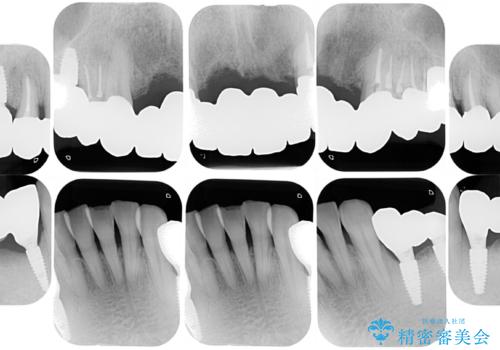

まずは歯周病の治療と抜くしかない歯を抜き、インプラント治療とセラミック治療を行いました。

治療中でも見た目が問題ない様に仮歯を製作していきますが、今回は奥歯に仮歯を入れることが不可能であったため、インプラントが使用できるまでの半年間は入れ歯を使用して頂きました。